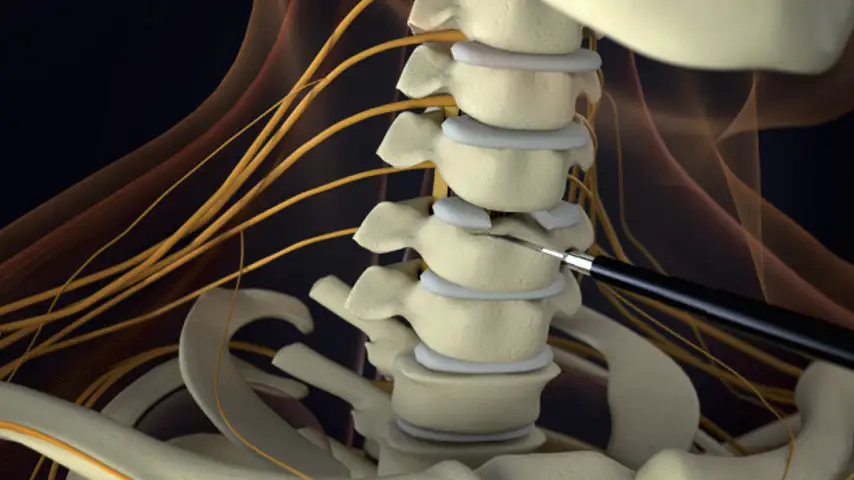

Selective osteotomies, safety on soft tissues

Laminotomy and Laminectomy

Correction of Deformities

Removal

of Osteophytes

Selective cut preserves soft tissue. (Dura, neves and vessels)

Cold osteotomy avoids bone necrosis

Increased surgical control & flexibility in bone cutting

Micrometric cut for minimal bone loss